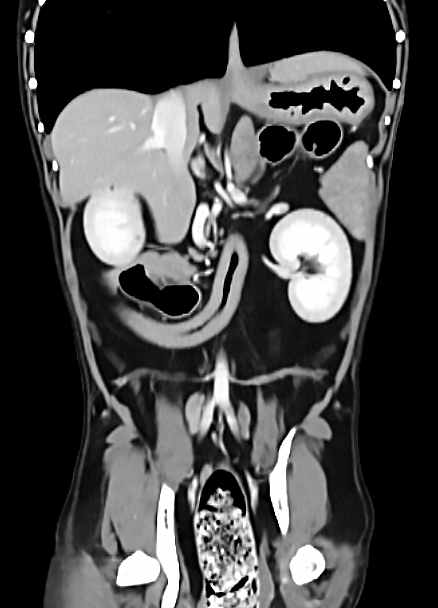

CT (Computed Tomography, 전산화 단층촬영) 검사는 X-ray를 이용해 반려동물의 몸을 여러 각도에서 촬영하고, 이를 컴퓨터로 합성하여 단면 이미지(슬라이스)를 만들어내는 정밀 진단 장비입니다.

사람 병원에서도 널리 사용하는 기술로, 뼈, 장기, 혈관, 종양 등 몸속 구조를 3차원(3D)으로 시각화할 수 있습니다.

| 복부 | 간, 비장, 신장, 위장관 종양 및 결석, 부신, 림프절 등 |